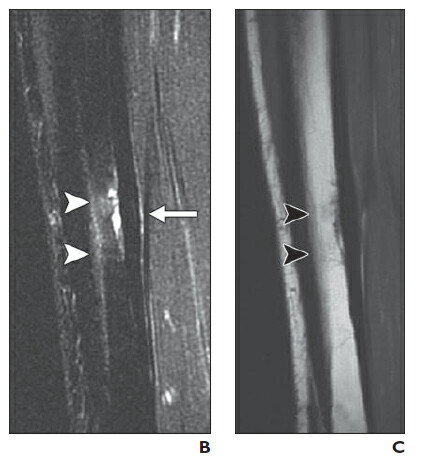

- Best – CT, MRI & Bone Scan